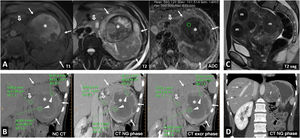

Multiple sporadic bilateral renal tumours that are histologically concordant. (A) Bilateral lipomas or angiomyolipomas with an almost exclusively fatty component (arrows) were found incidentally on non-contrast CT in a 65-year-old man with no other clinical or radiological features suggestive of tuberous sclerosis. (B) Bilateral papillary renal cell carcinoma (pRCC). A 78-year-old male, under follow-up for a mildly hyperattenuating left renal tumour found incidentally in a non-contrast study with low enhancement (study not shown). In the follow-up examination (left; axial composite image) moderate growth is observed (arrow), with another contralateral lesion (dashed arrow) going unnoticed. A partial left nephrectomy was performed. Image from another follow-up examination two years later (right) shows the area that underwent the partial nephrectomy (hollow arrow) and the contralateral lesion which has grown (dashed arrow). An ultrasound-guided core needle biopsy was performed. The histological result in both cases was pRCC, which was then classified as type 1. The patient opted for active surveillance, and slight growth of the right lesion was observed in the only follow-up examination, performed one year later (not shown). (B) Bilateral clear cell renal cell carcinoma (ccRCC). A 67-year-old male with haematuria. CT scan in the nephrographic phase shows an upper right renal lesion (arrows) with intense enhancement peaking in the corticomedullary phase (not shown) and central areas of necrosis, corresponding to a ccRCC pT3 pN1 after nephrectomy, and a smaller lower left lesion (arrow) with intense and slightly heterogeneous enhancement. This lesion was removed and histologically confirmed as pT1a. No germline mutation for Von Hippel-Lindau was detected and there were no other tumours in the right nephrectomy specimen. (D) Bilateral oncocytic neoplasms in a 75-year-old male. Incidental finding of two small upper lesions with moderate enhancement on average coronal image of spectral acquisition in nephrographic phase (arrows), with iodine density of 3.1 mg/mL on the iodine map of the same study in the right lesion, 4.6 in another ipsilateral lesion, and 3.2 in the left lesion (not shown). A core needle biopsy was performed on the right lesion, which resulted in an oncocytic diagnosis. The same histology was assumed for the rest of the lesions which behaved similarly. The result from the single-gene test for Birt-Hogg-Dubbé was negative. The patient opted for active surveillance.

Multiple forms of coexistence of histologically different tumours have been described 11 (Fig. 2).

Multiple sporadic bilateral renal tumours with discordant histology. (A) Contralateral clear cell (ccRCC) and papillary carcinomas (pRCC). ccRCC on right (arrows). Lesion with significant enhancement and eccentric necrotic areas on coronal and axial CT images in corticomedullary phase. pRCC on left (hollow arrows). Lesion homogeneously hypoenhancing. Arrowheads: hepatic haemangioma. (A) Contralateral ccRCC and chromophobe carcinomas. Upper left: Baseline CT (axial image in nephrographic phase). Incidental finding of well-demarcated right lower renal nodular lesion with moderate enhancement, less than that of the adjacent renal parenchyma (arrow). A contralateral cortical lesion with more intense enhancement, very similar to that of the renal parenchyma (dashed arrow) was overlooked. A right nephrectomy was performed revealing a pT1a cRCC. A review three years later revealed this lesion, with moderate growth (not shown). Six years after the first study, spectral CT was acquired (upper right: average image; lower left: virtual non-contrast image; lower right: iodine map), which again demonstrated moderate growth during the interval and iodine density of 6.8 mg/mL. Core needle biopsy revealed a pT1a ccRCC following partial nephrectomy.